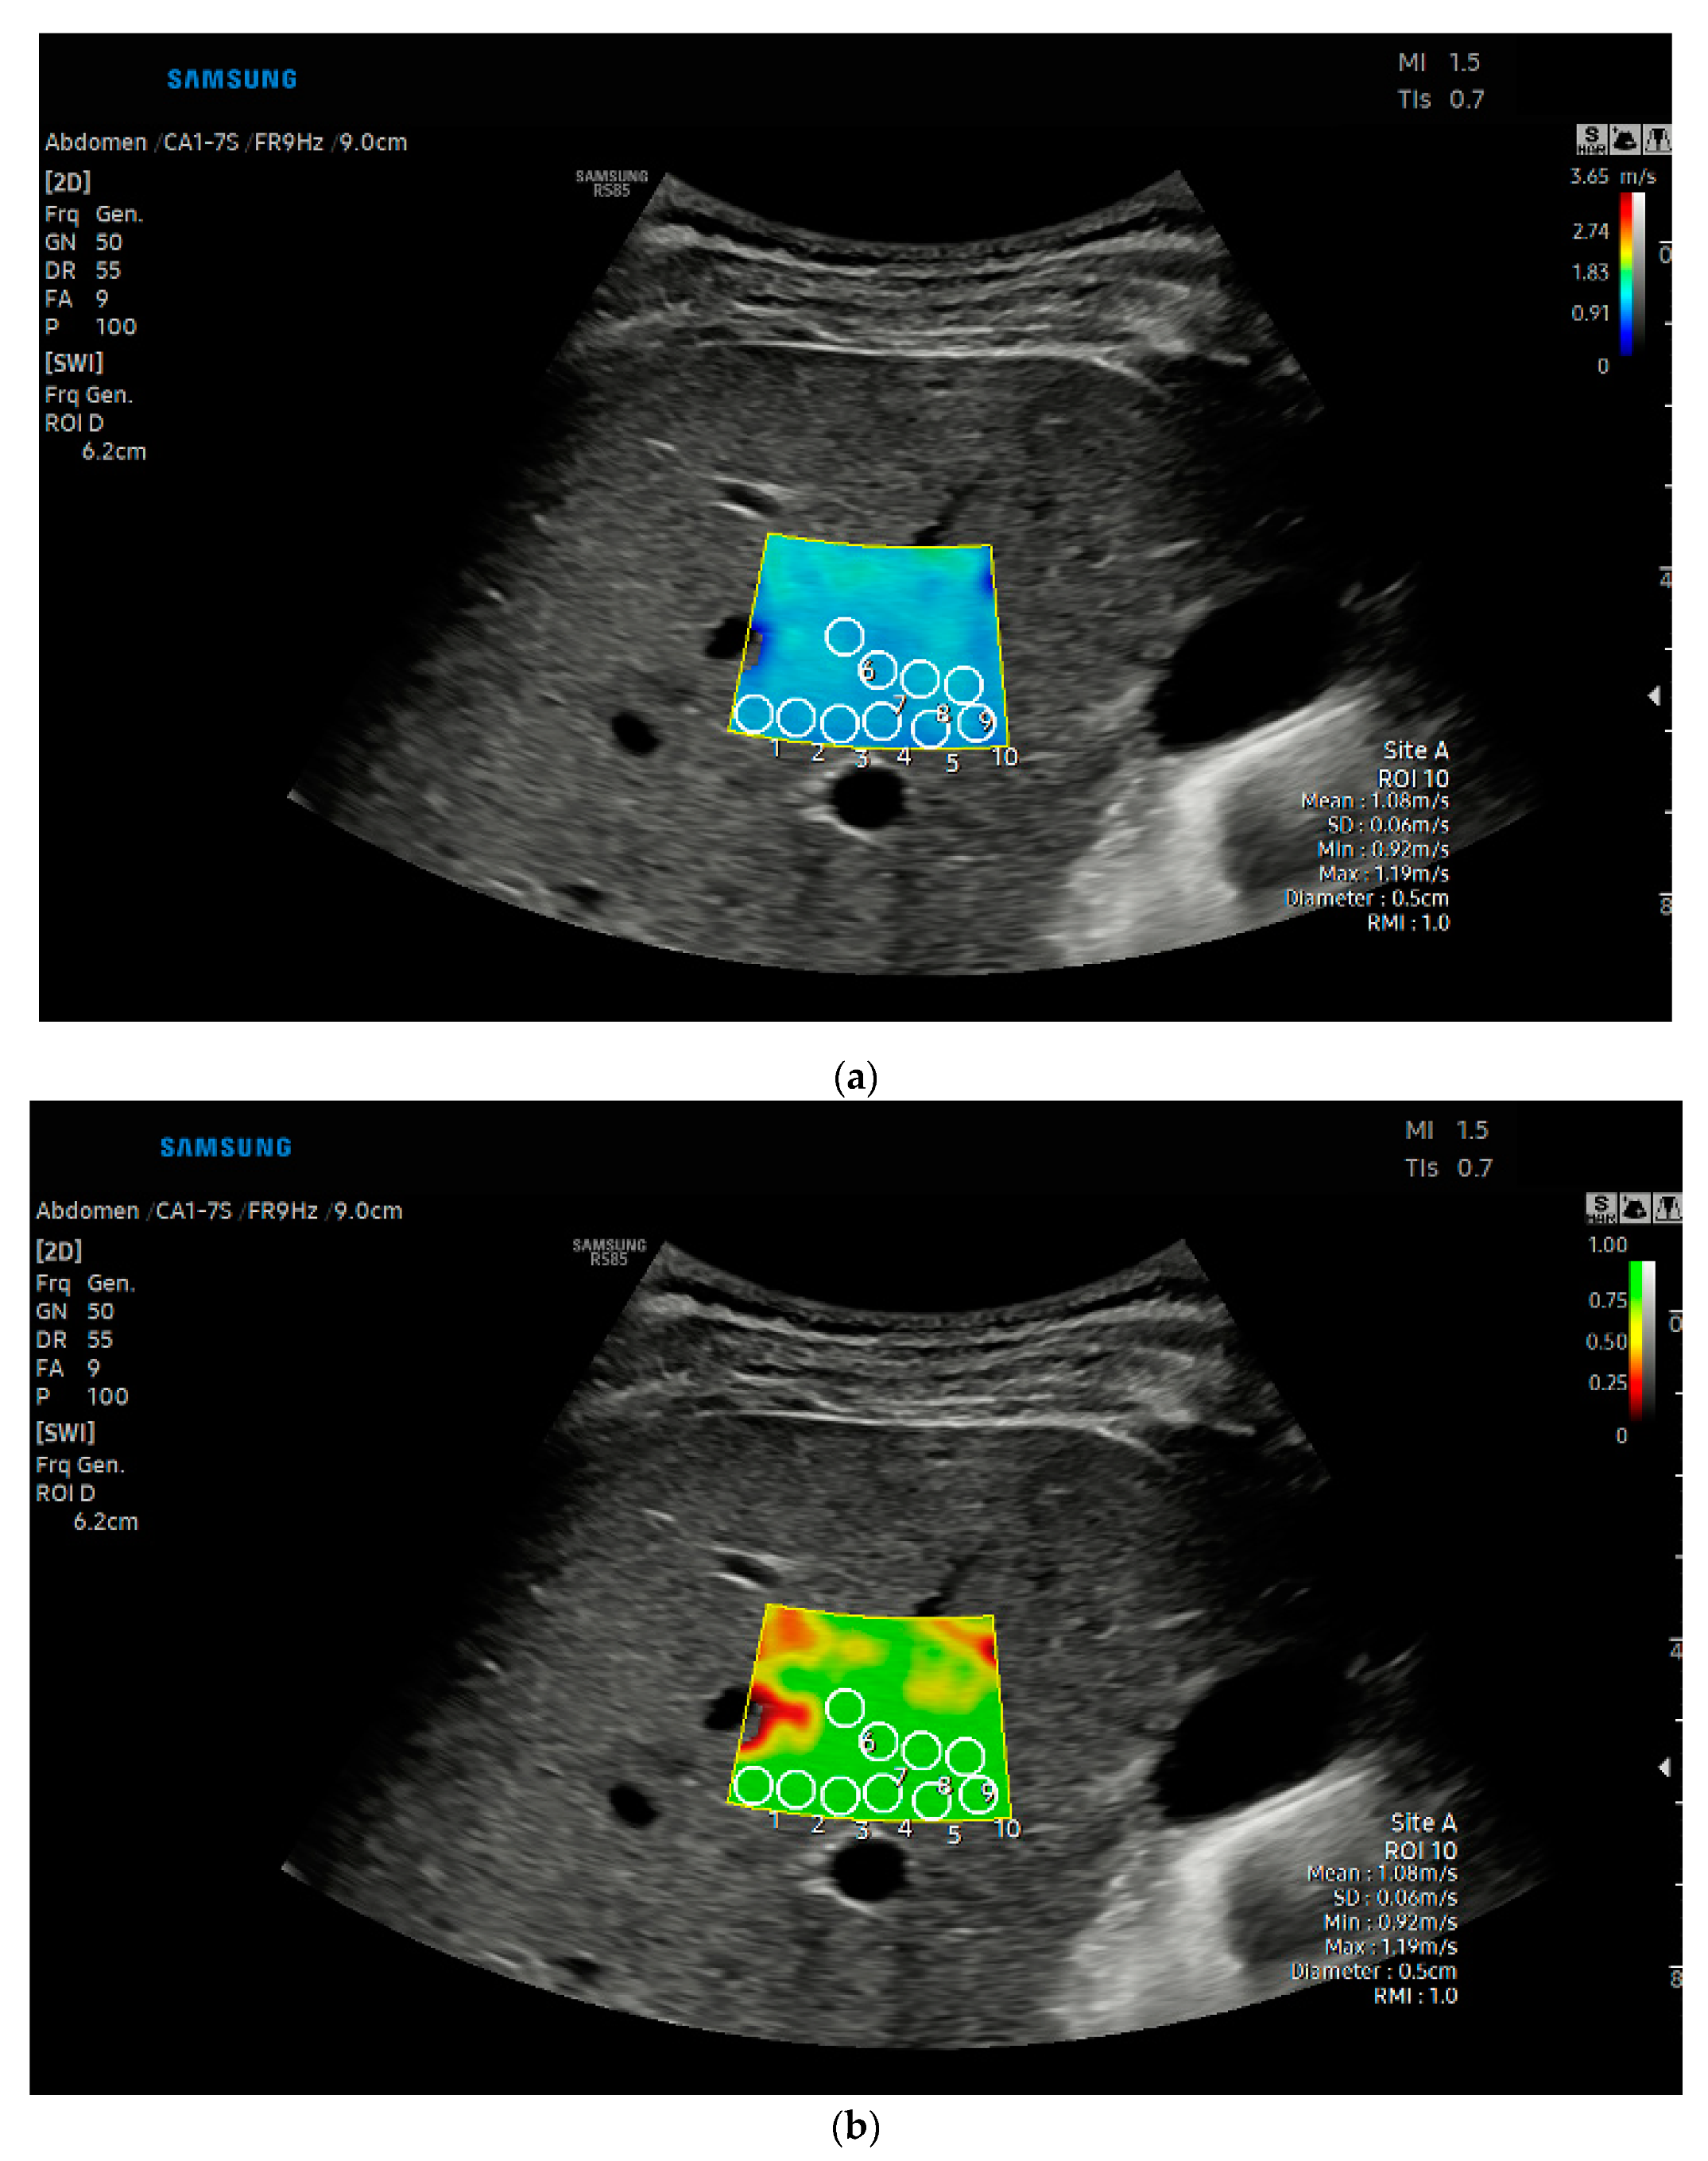

2.2. Liver Stiffness Measurements with Shear Wave Elastography